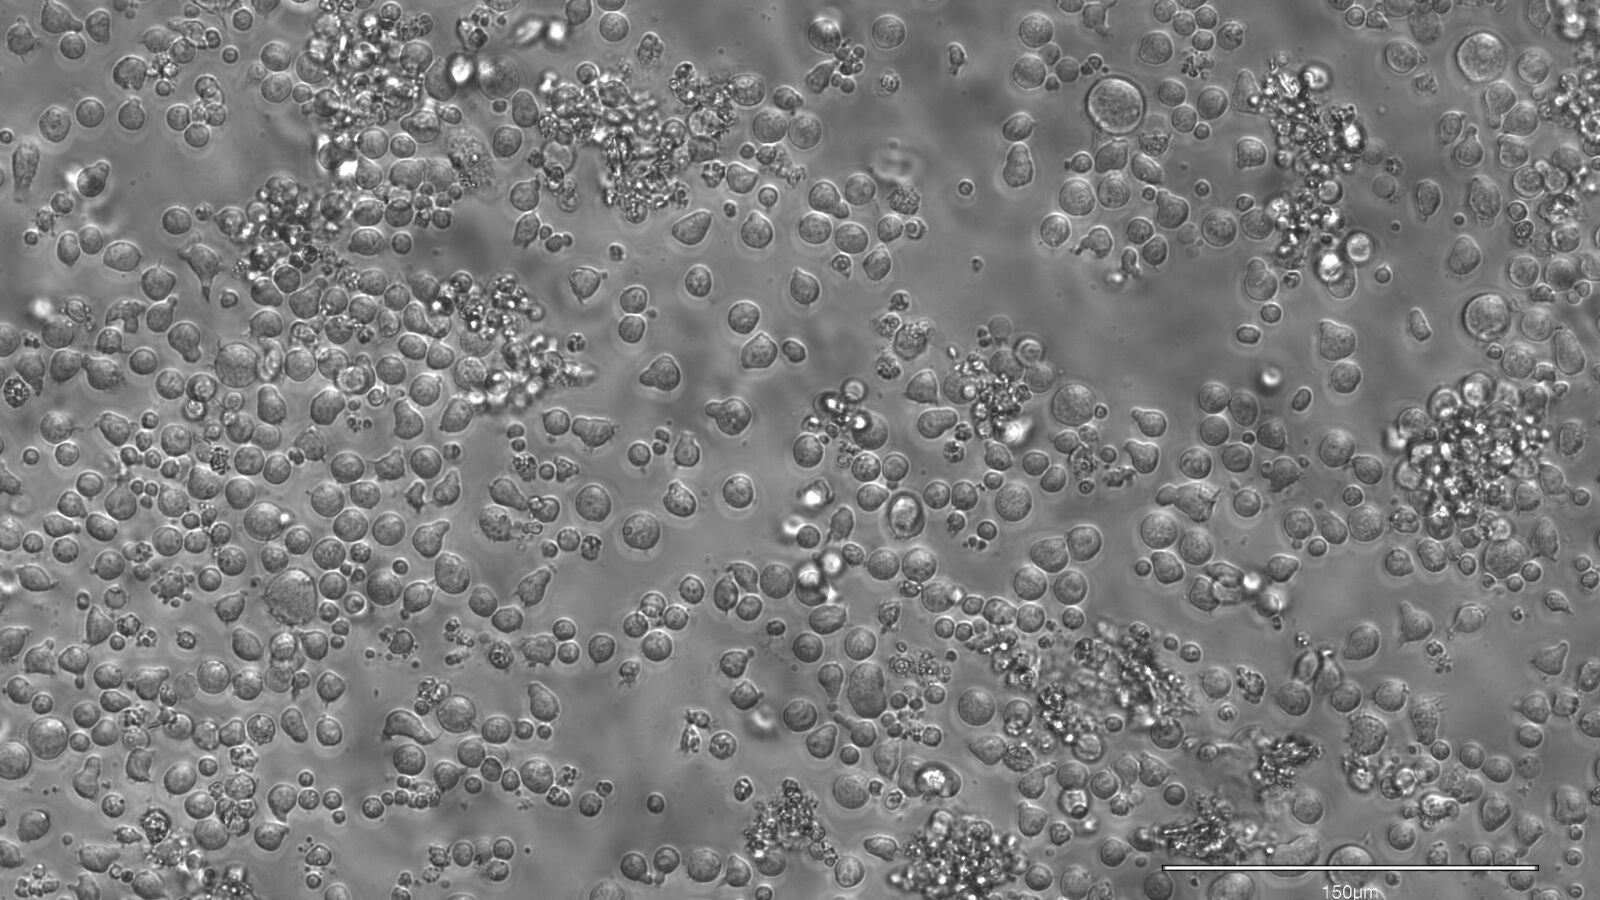

Por lo tanto, conocer cómo envejece la sangre es clave. Se sabe que, en población joven, hay en torno a unas 150.000 células madre sanguíneas activas, las cuales son responsables de producir cerca de 100 a 200 millones de células sanguíneas nuevas cada día. Con el transcurso de los años, algunas de estas células madre se extinguen y otras se expanden, lo que se relaciona con un aumento de la inflamación y el inicio de estas enfermedades.

Gracias a ello, los investigadores pudieron observar que en la sangre de las personas jóvenes hay una gran cantidad de células madres diferentes, las cuales producen un conjunto diverso y variado de células, mientras que a edad avanzada, principalmente a partir de los 50 años, unas pocas se imponen a sus vecinas, tomando gradualmente el control de la producción de sangre. A partir de los 60 años de edad, este fenómeno es aún más evidente y pronunciado.